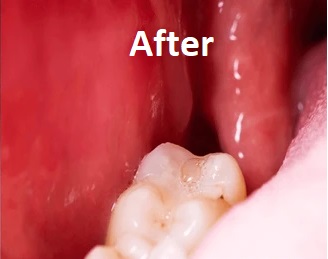

The Result

Wisdom teeth removal provides:

• Relief from pain and infection

• Improved oral hygiene

• Prevention of future dental problems

• Faster recovery with proper care

Patients often experience significant improvement in comfort and oral health after the procedure.